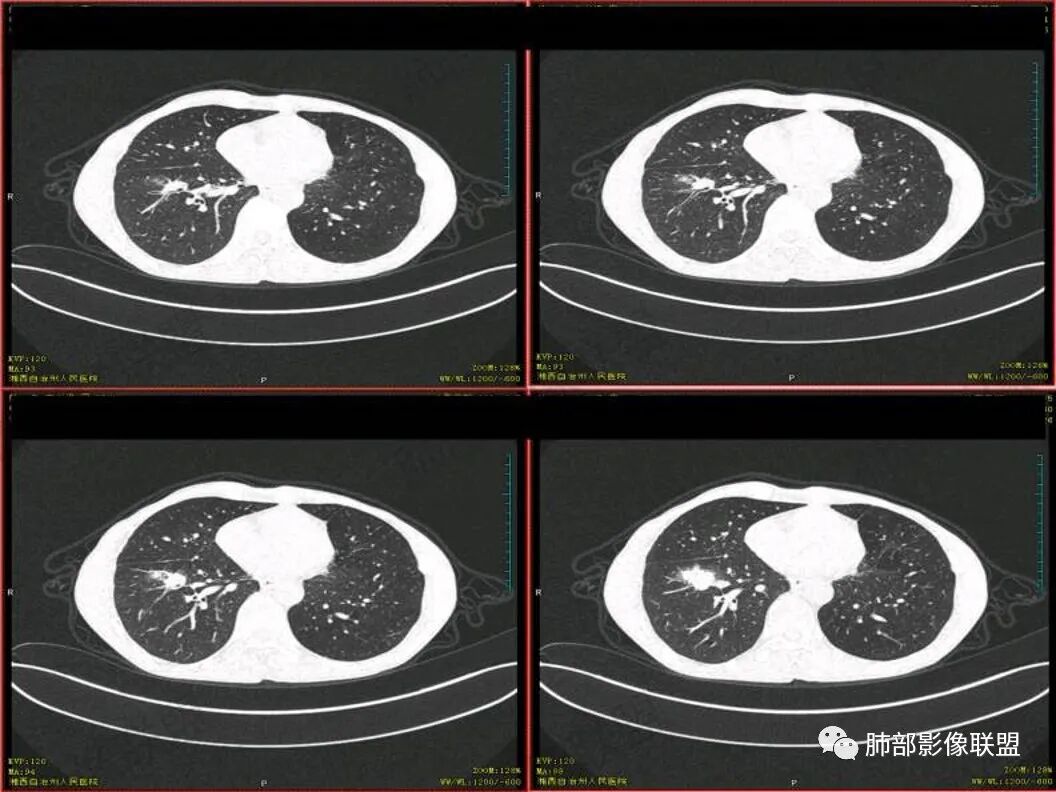

胸CT可见右肺下叶前基底段占位性病变,病灶周围可见周围不清毛玻璃影,病灶边缘可见分叶,呈膨胀性生长,纵隔窗可见病灶内呈偏心性坏死,增强扫描静脉期强于动脉期,纵隔隆突下淋巴结可见肿大坏死。

双上肺多发病灶,考虑结核(陈旧灶为主),右肺下叶前基底段占位,分叶、毛刺、胸膜牵拉,中央坏死,局部壁不光滑,前基底段支气管未见显示,不均匀强化,病灶远端阻塞性炎症,纵隔淋巴结肿大、融合。综合考虑恶性病变,鳞癌可能大。

临床 中年男性,咳嗽盗汗、老结核史,血沉高、t试验阳性,结核应该存在,cyf高4倍,价值怎么样待验证。影像 :两上肺实变加粗大索条灶,两肺野弥漫粟粒,考虑结核应该问题不大。重点分析右下病灶:隆突下淋巴结肿大,但伴钙化,有边缘强化?淋巴结融合又是恶性征像?右下肺病灶冠状位总体方正,横断位总体三角型,长毛刺、近端也有渗出、坏死彻底、空洞壁光滑锐利,似有边缘强化?看做薄壁空洞?以上符合炎性病灶。   支持恶性的征像 :冠状位的空洞似有壁结节,偏心坏死。   综合 ,右下肺鳞癌(偏心空洞+cfy)+两肺结核。

右下叶前基地段肿块,不规则边缘,周围树丫和长短毛刺,内部小空泡,强化后环形强化,纵膈淋巴结肿大,并有不规则环形强化和钙化,总体考虑感染性病变,结核病。

老年男性,既往有肺结核病史。影像双上肺病灶考虑陈旧性肺结核病灶,关键是右下肺团块影,从视频看,右下叶前段分支有堵塞,病灶局部膨隆,有分叶,周围有磨玻璃,但边界不大清楚,远端还有可以阻塞性炎征象,内部有偏远心端坏死,故考虑恶性可能性大。

影像表现为 双肺上叶多发索条斑片影,可见支气管牵拉性扩张,考虑为陈旧肺结核纤维硬结灶。右肺下叶前基底段团块影膨隆生长,边界不清,呈分叶,毛刺,胸膜牵拉,支气管截断,中央区坏死明显,但未形成空洞,坏死区边缘光整,不均匀环形强化,隐约见壁结节。纵隔淋巴结肿大伴钙化,病灶远端见阻塞性炎症,结合CYFRA21-1偏高,应想到考虑恶性病变,鳞癌可能性大。